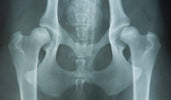

Hüftdysplasie ist eine erbliche Erkrankung, bei der Hüftpfanne und Hüftkopf nicht richtig zusammenpassen. Dadurch entsteht ein instabiles Gelenk, das mit der Zeit verschleißen und Schmerzen verursachen kann. Am häufigsten tritt sie bei großen Hunderassen wie Deutschen Schäferhunden, Labrador Retrievern und Golden Retrievern auf, aber auch kleinere Rassen können betroffen sein.

Foto von: licg